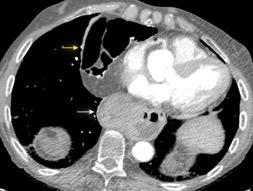

T. mixto de células germinales del testículo izquierdo

Nódulos pulmonares múltiples. (flechas verdes). Masas paratraqueales. (flechas amarillas). Dudoso ensanchamiento retrocrural (flechas negras). sigue….

Ttawfik A et al. Trans-diaphragmatic Pathologies: Anatomical Background and Spread of Disease on cross-sectional Imaging. Current Problems in Diagnostic Radiology. 2021.

T. mixto de células germinales del testículo

izquierdo Metástasis pulmonares. (flechas verdes). Ganglios paratraqueales. (flechas amarillas). Ganglios retroperitoneales (flechas negras)

Tawfik A et al. Trans-diaphragmatic Pathologies: Anatomical Background and Spread of Disease on cross-sectional Imaging. Current Problems in Diagnostic Radiology. 2021.